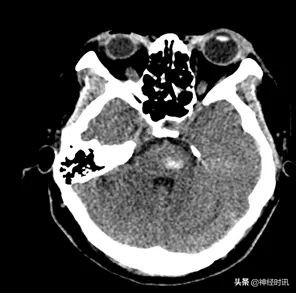

入院后第1天复查CT:与入院时对比,出血未明显增多

入院7 d,脑血疏口服液用药5 d后复查CT:脑干出血,较入院时片状密度影减低